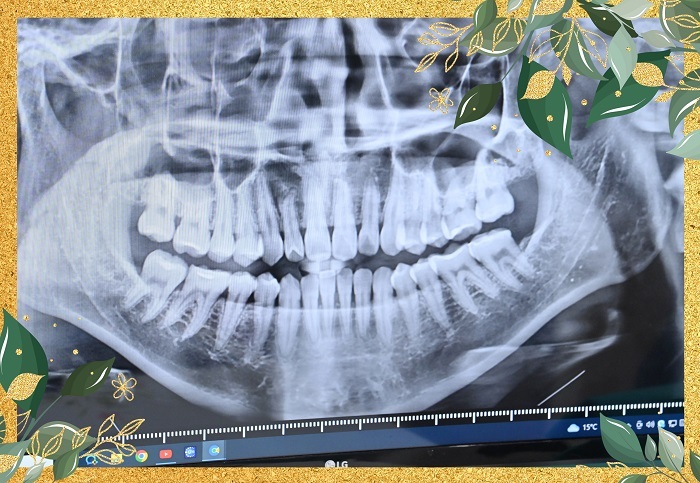

踏入診療間檢查前會有一個流程是要拍攝X光片

護理人員說明拍X光片用意在於讓牙醫師了解口腔有沒有蛀牙

進行陶瓷貼片療程是需要將有蛀牙的地方先做治療

醫師才能做後續貼片相關安排

斷層掃描間裡儀器轉完一圈

果不其然在外面螢幕上每顆牙齒健不健康當場一覽無遺

連之前曾經在別間牙科做植牙也逃不過X光片法眼